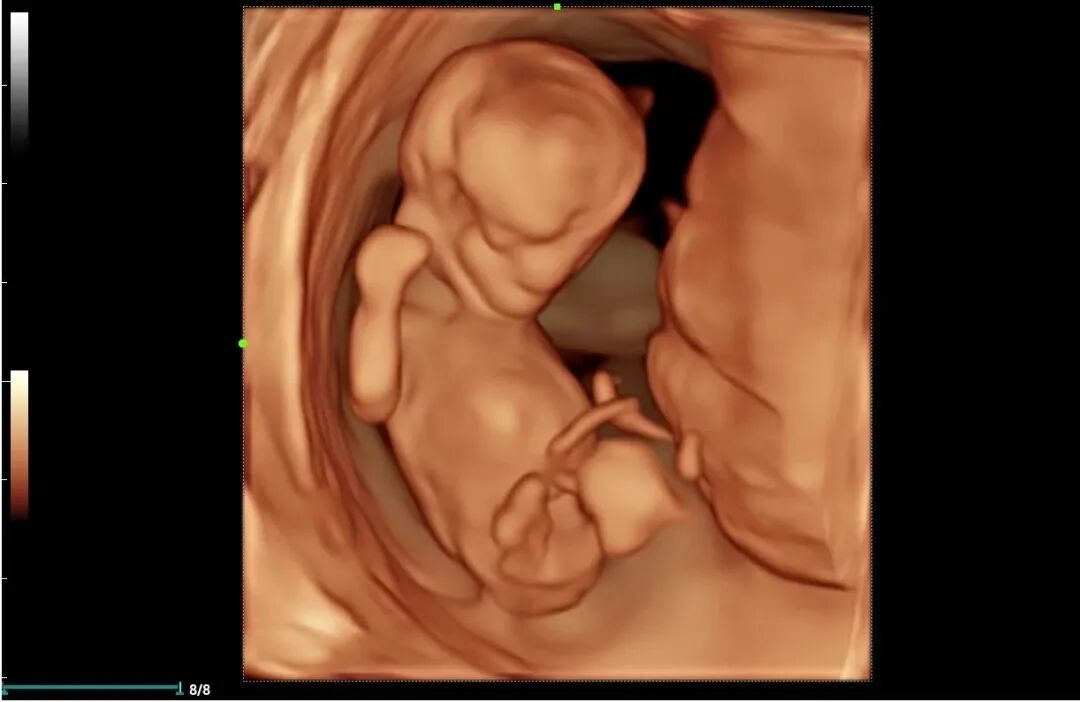

为进一步提高我院诊疗检查与诊断水平,不断满足城乡患者日益增长的就医需求,健全和完善医疗保障体系。2022年12月我院引进了mindray- Resonal9T高端彩色多普勒超声系统正式投入使用,此设备具备超声介入、超声造影、超声高帧率 STE 剪切波弹性成像及应变式弹性成像(甲状腺、乳腺、肝脏),二维、三维、四维、阴式、盆底、心脏及血管超声等功能。此设备的引进标志着海伦影像学科将跨越新的高度,以此助力城乡百姓解决看病难,看病贵的就医难题!